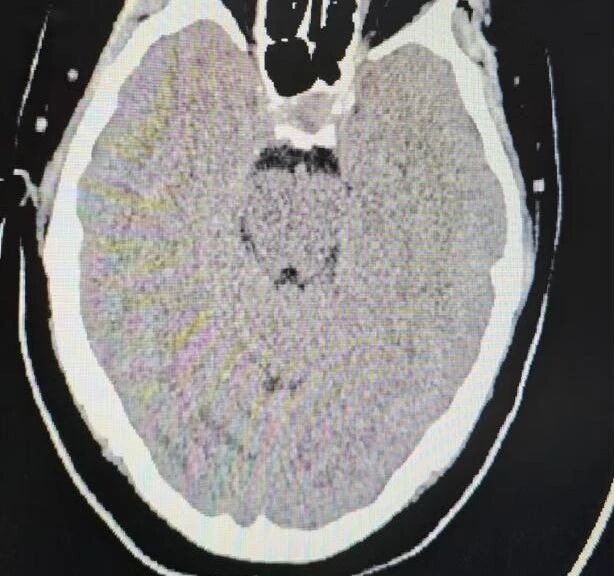

阿女士到达我院后,急诊团队迅速开展气管插管、呼吸机辅助通气、抗癫痫及镇静等紧急处置。经进一步影像检查,卒中团队明确诊断为颅内静脉窦非脓性血栓形成,伴症状性癫痫及脑出血,是一种危险性极高、进展迅速的急危重症。援疆专家、神经内科主任林镇洲在评估后立即作出决定:必须紧急取栓,尽快恢复颅内静脉回流,才能最大限度保护患者生命和脑功能。

在与时间赛跑的抢救中,林镇洲与神经内科副主任阿地力江·阿布力米提主刀,迅速为阿女士实施经皮颅内静脉取栓术联合经皮颈静脉球囊扩张成形术。手术采取微创介入方式,通过颈静脉穿刺,将导管精准送达血栓阻塞部位,在影像引导下将血栓吸除、捕捉并清理干净,同时利用球囊撑开狭窄段,进一步改善静脉回流。这种方式无需开颅,创伤小、速度快,能够迅速降低颅内压力,是目前救治静脉窦血栓的关键手段之一。